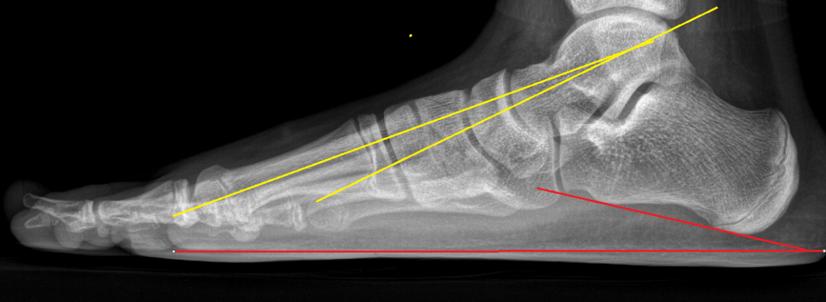

X线示足弓消失